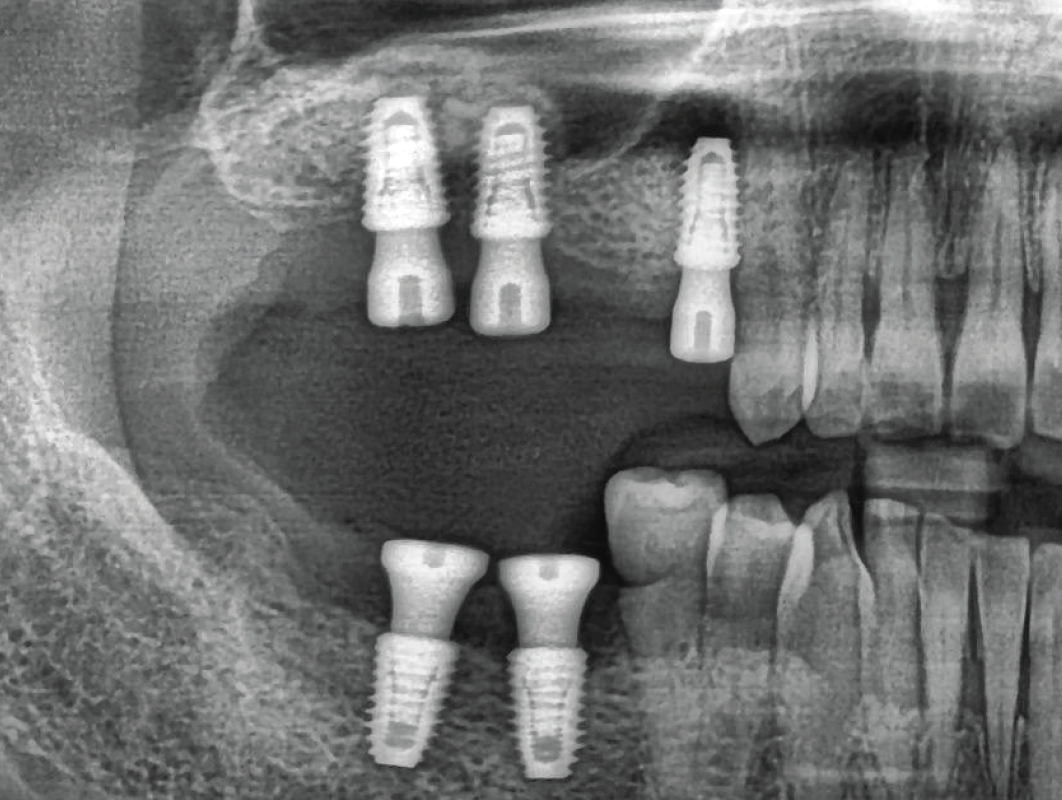

PRE-RACE DIAGNOSTICS – PREOPERATIVE ASSESSMENT

Radiographic and Clinical Evaluation – Scouting the Route

Just like drivers need a map of the race track, surgeons need a clear view of the sinus structure. We’ll cover CBCT analysis and key anatomical landmarks to keep you in the race

Radiographic and Clinical Evaluation – Scouting the Route

Just like drivers need a map of the race track, surgeons need a clear view of the sinus structure. We’ll cover CBCT analysis and key anatomical landmarks to keep you in the race

OFF-ROADING – HANDLING COMPLEX CASES

The Terrain Gets Tougher

When sinus anatomy is severely atrophic, it’s like driving off-road. We’ll cover modifications to handle the “rougher terrain” of complex sinus cases.

Sinus Floor Elevation with Implant Placement – Timing is Everything

Like perfectly timed gear shifts, the sequence of sinus lifts and implant placements is key. We’ll cover when to “accelerate” and when to hold back for best outcomes.

01

OFF-ROADING – HANDLING COMPLEX CASES

The Terrain Gets Tougher

When sinus anatomy is severely atrophic, it’s like driving off-road. We’ll cover modifications to handle the “rougher terrain” of complex sinus cases.

Sinus Floor Elevation with Implant Placement – Timing is Everything

Like perfectly timed gear shifts, the sequence of sinus lifts and implant placements is key. We’ll cover when to “accelerate” and when to hold back for best outcomes.

VICTORY LAP – CASE STUDIES AND GROUP DISCUSSION

Reviewing the Big Races

Like debriefing a race, we’ll go through real-life case studies, analyzing successes and setbacks. Group discussion will help refine your skills for future “races” in the surgical field.

Reviewing the Big Races

Like debriefing a race, we’ll go through real-life case studies, analyzing successes and setbacks. Group discussion will help refine your skills for future “races” in the surgical field.